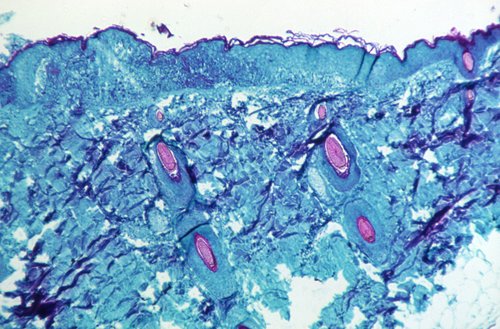

Bolest se očituje povišenom temperaturom, glavoboljom, zimicom, isrpljenošću, umorom, bolovima u mišićima i leđima, oticanjem limfnih čvorova i osipom kao kod vodenih kozica.